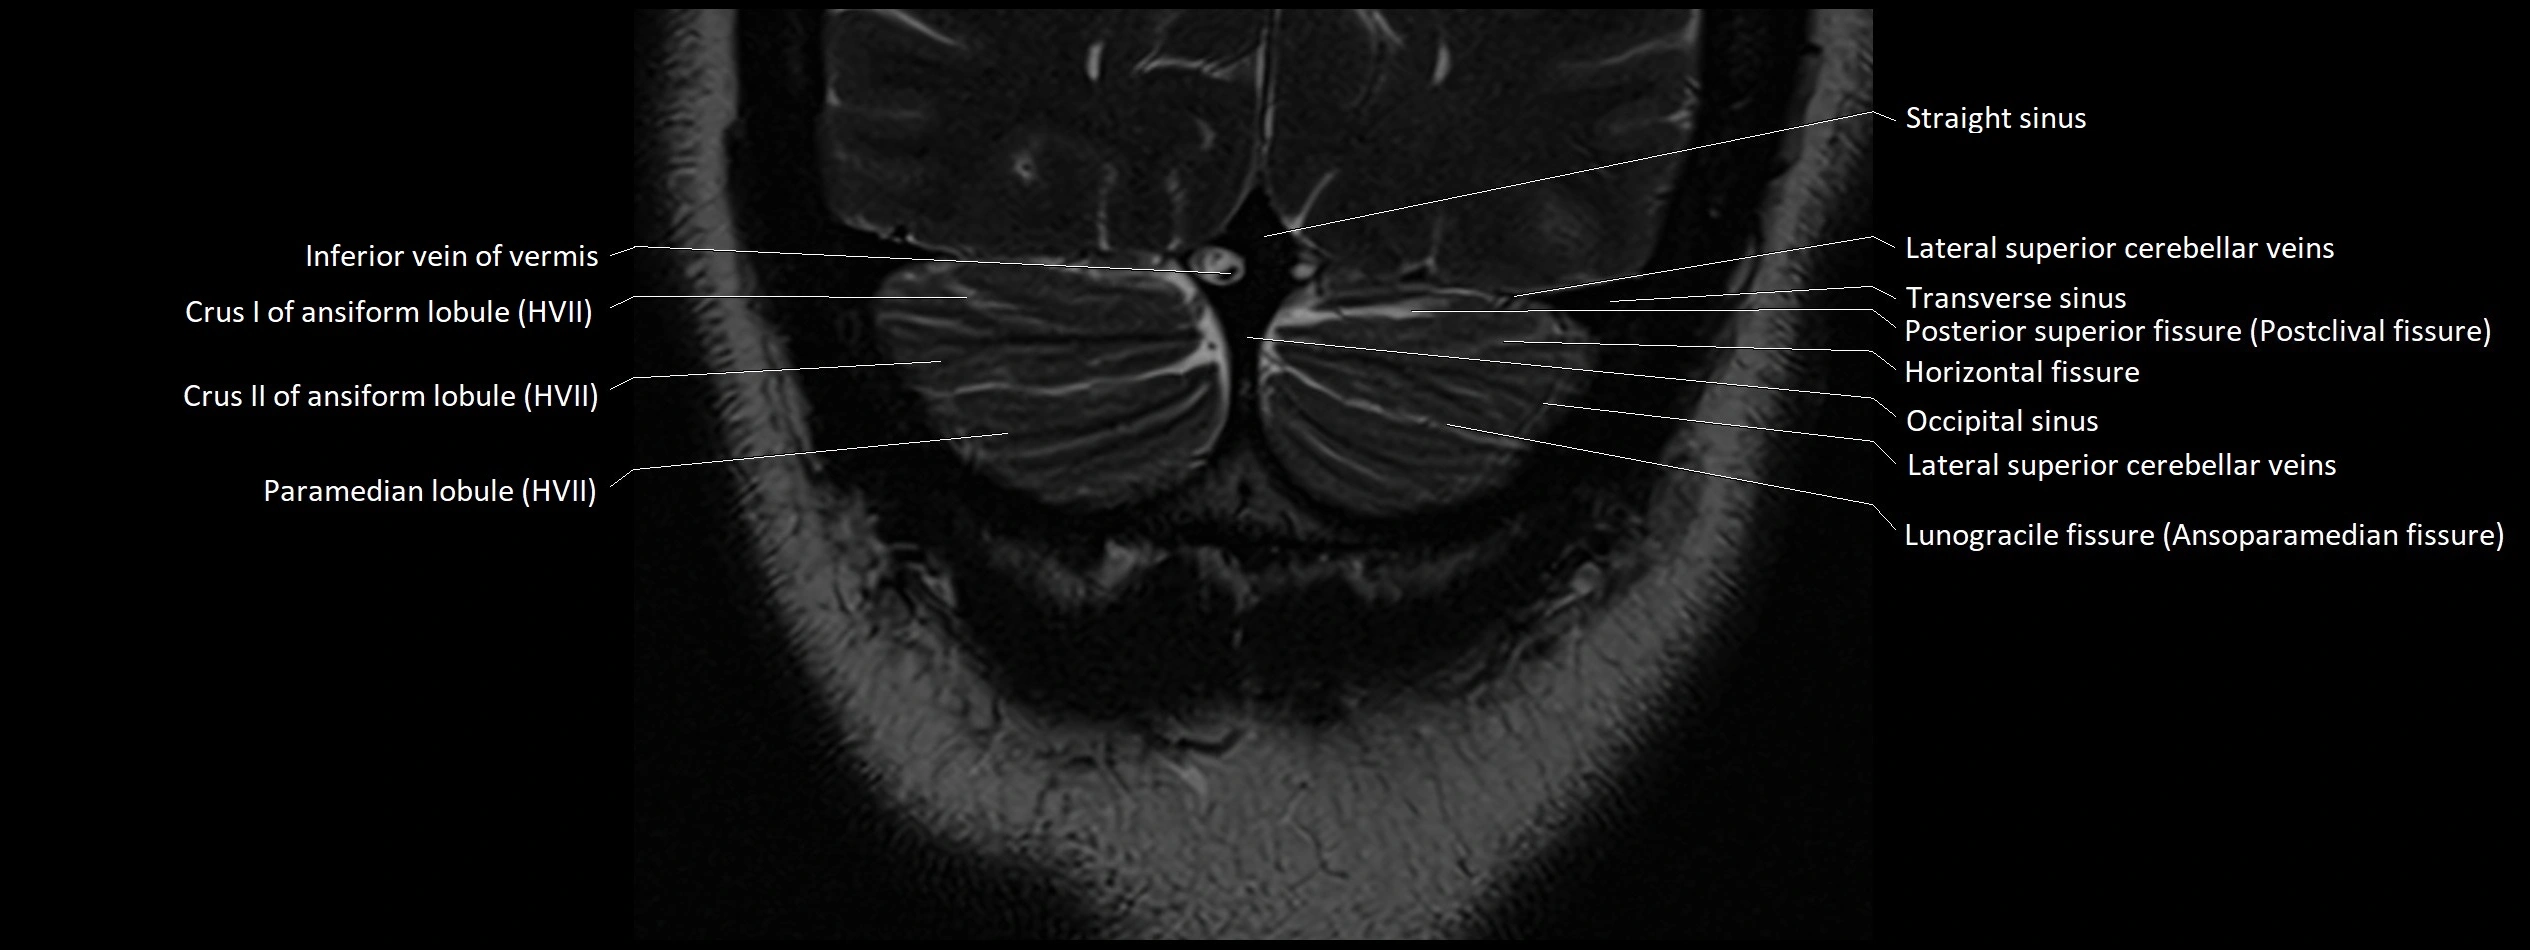

MRI images